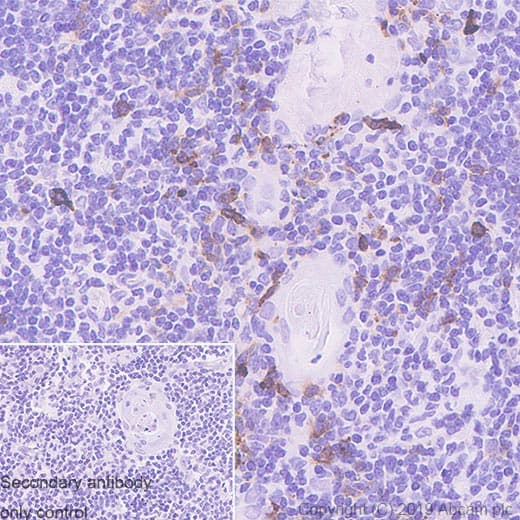

Anti-CD134 / OX40L receptor antibody [EPR23001-88] - BSA and Azide free(ab264469)

Rabbit Recombinant Monoclonal CD134 / OX40L receptor antibody. Carrier free. Suitable for IP, Flow Cyt, WB, IHC-P and reacts with Human samples.

Applications Flow Cyt, ICC/IF, IHC-P, IP, WB

Species Reactivity Human